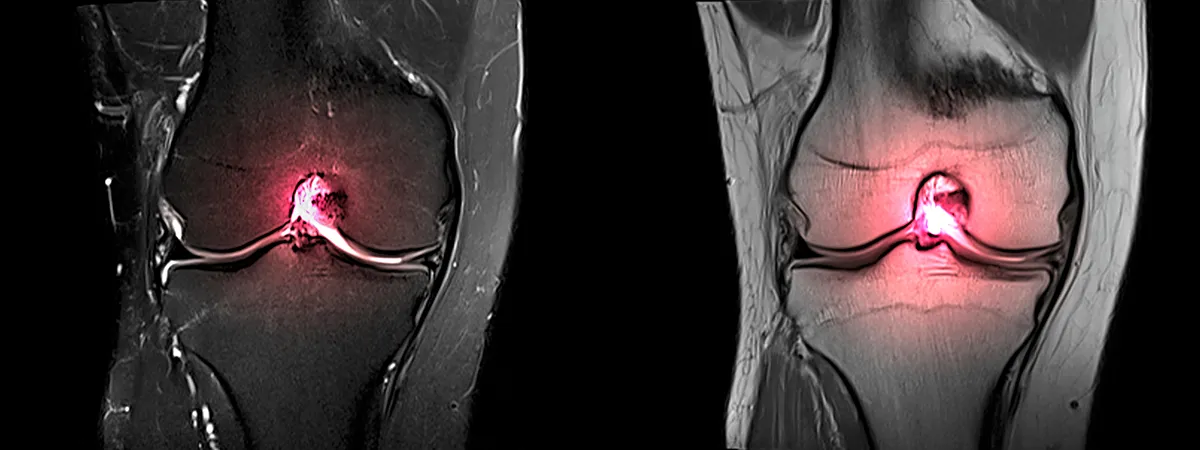

Le diagnostic est alors complété par des radiographies et par une IRM qui permettent de visualiser la rupture, de mesurer la laxité et de rechercher des lésions associées méniscales, cartilagineuses ou ligamentaires.